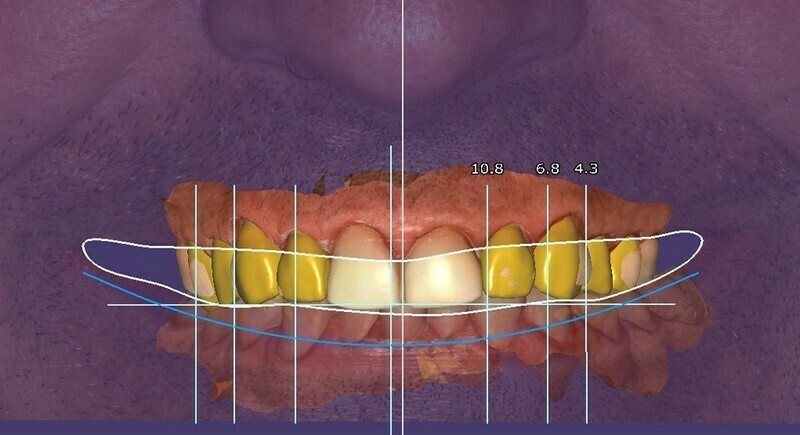

Le patient a 52 ans et il s’est usé les dents avec une brosse-à-dent très dure. Il a pensé bien faire en buvant beaucoup de jus de citron et en se faisant des bains-de-bouche à la chlorhéxidine. Nous sommes face à une abrasion d’origine mécanique et chimique et à des colorations dentaires d’origine médicamenteuse.

Des images photographiques en 2D et des images en 3D ont été couplées pour concevoir la réhabilitation du sourire et la proposer au patient.

L’occlusion (rencontre des dents) est optimisée.

Résultat final.

A l’aide d’un jeu de maquettes et d’usinage, les restaurations respectent le projet initial.